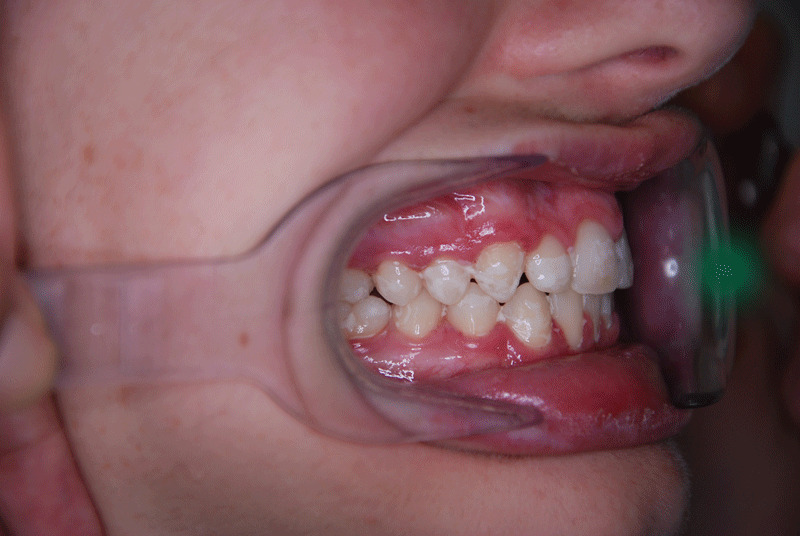

La sobremordida, lo que coloquialmente se conoce como mordida profunda, es un problema de maloclusión en que los dientes de arriba están adelantados y cubren excesivamente a los inferiores. Por lo tanto, podemos afirmar que existen distintos grados de sobremordida.

La causa más común se debe a que la mandíbula inferior (o maxilar) es pequeña. Cuando ello se produce, los dientes superiores se ven “adelantados” y los incisivos inferiores siguen saliendo y creciendo hasta llegar a tocar la mucosa del paladar o techo de la boca. Se pueden producir heridas traumáticas o úlceras en el paladar que pueden producir un malestar o un dolor considerables.

Si existe la falta de algún incisivo (agenesia o falta de pieza dental), se produce una situación parecida a tener una mandíbula pequeña. En ocasiones, ocurre que los dientes posteriores tampoco cierran bien.

El patrón braquifacial de crecimiento de la estructura facial (patrón de cara más ancha y corta que no alargada) es el que más se relaciona con la mordida profunda. Normalmente, estos patrones son maloclusiones de clase II, tanto dental como esquelética.